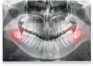

Our oral and maxillofacial surgeon, Dr. Michael Shnayder, provide treatment for a wide variety of issues relating to the mouth, teeth, and facial regions. Dr. Michael Shnayder practices a full scope of oral and maxillofacial surgery with expertise ranging from dental implant surgery and wisdom tooth removal to facial trauma and oral pathology. This also includes techniques designed to rebuild bone structure with minimal surgical intervention and optimal patient comfort. Our team can also diagnose and provide treatment for facial pain, facial injuries, and fractures. Our caring oral surgeon and team provide excellent customer service in addition to quality surgical services. We are proud to treat children as well as adults. Many of our patients have anxiety, so we provide a comfortable, calming environment to help them. Our oral surgeon and team work together as a unit, not as individuals.

Our office uses the latest in technology so that we can provide you with the best care possible. We use a CT scanner to produce 3D images of your teeth, soft tissues, bone, and nerve pathways in just one scan. This helps us to effectively plan your treatment. We also have a digital impressions machine, which does not use the messy paste of traditional impressions. Since 2011, we have provided oral and maxillofacial surgery in Omaha, Nebraska, and the surrounding areas of Elkhorn, Blair, Bennington, Bellevue, Council Bluffs, Fremont, and Norfolk, Nebraska. We welcome you to contact Village Pointe Oral Surgery today to learn more about us and to schedule an appointment.